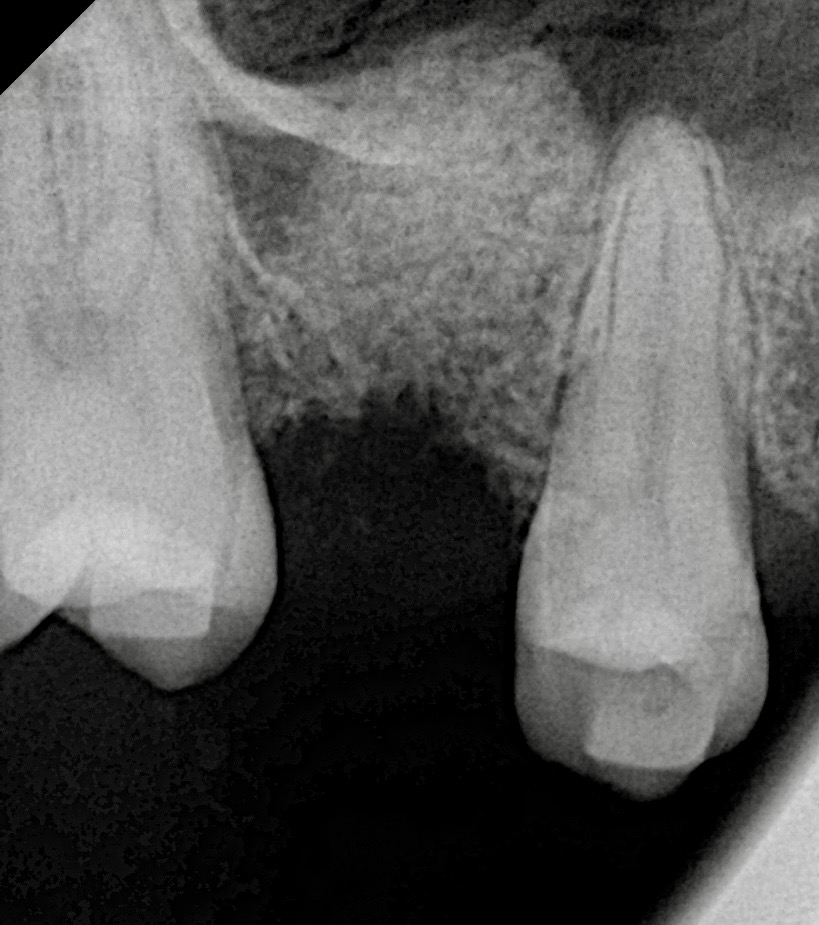

The patient presented with a missing maxillary first molar and reduced residual ridge height of approximately 6 mm (Fig 1). A CBCT scan revealed adequate bucco-palatal width and sinus floor proximity, indicating the need for a crestal (indirect) sinus lift rather than a lateral window procedure.